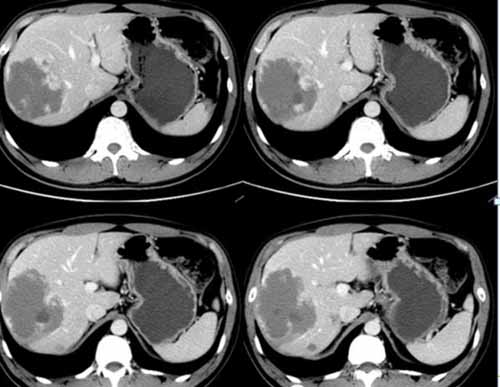

(術(shù)前右肝肝包膜下巨大血管瘤)

(術(shù)后復(fù)查肝血管瘤固縮,栓塞劑沉積良好,無復(fù)發(fā))